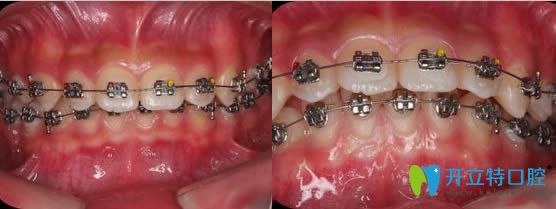

這就是我做矯正前的牙齒照片,是不是看著很奇怪,好像下面的幾顆牙齒消失了。自從戴牙套后,感覺(jué)牙齒每個(gè)月都有明顯的變化。

第五個(gè)月上面一排的牙齒逐漸排列整齊了,那顆凹下去的牙齒被拉上來(lái)了。

第六個(gè)月那顆被擠在靠上的位置的虎牙也基本被拉下了來(lái)了..............